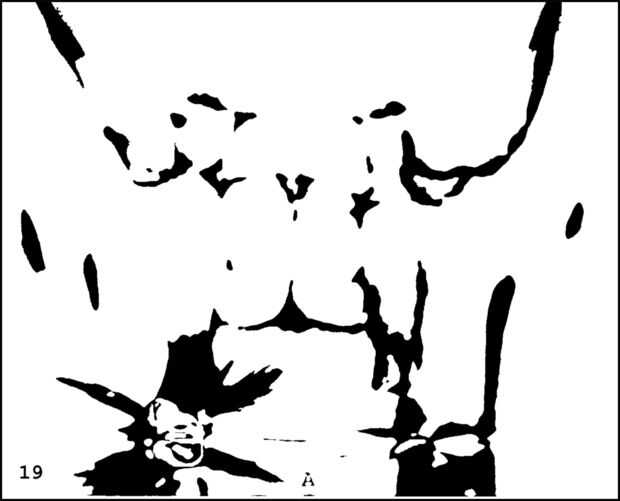

¡ Wow! Este fue por menos de 12 horas y tengo 1.000 visitas! Esto es sólo mi segundo instructable, así que estoy encantada. Decidí seguir adelante y publicar las imágenes que utiliza. Se trata de MRI de mi esposa, así que ella sólo puede tener lo mundos primer código abierto jefe. Mi lámpara utiliza solamente las primeras 16 capas, pero te di todos 34 que representa. Seguir adelante y usar estas imágenes, pero si lo haces, por favor me manden una imagen de lo que te ocurrió así que puedo hacerla sentir un poco famoso. ¡Que te diviertas!